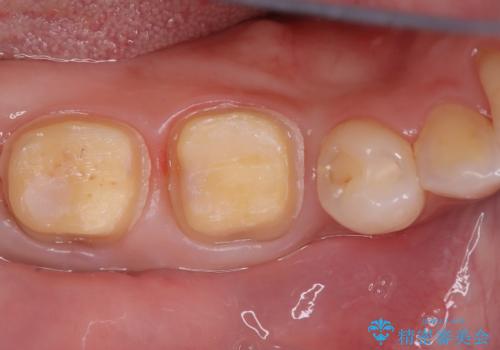

- 右下6番と7番の奥歯に、歯の根元部分の虫歯(根面カリエス)を認め来院されました。通常の虫歯よりも進行しやすい根面カリエスは、再発リスクを抑えた治療が重要です。患者様のご希望と口腔内の状態を考慮し、虫歯を徹底的に除去し、精密で耐久性の高いセラミッククラウンで修復する治療計画を立案しました。これにより、長期的な再発防止と咬み合わせの機能回復を目指します。

治療ではまず、感染した歯質をマイクロスコープで確認しながら慎重に除去。その後、セラミッククラウンを装着するための歯の形成を行いました。型取りから患者様の歯の形や色に合わせたオーダーメイドのセラミッククラウンを作製。セラミックは、プラークが付着しにくく、再治療のリスクを低減する特性があります。最終的に、精度の高いクラウンを装着し、咬み合わせを細かく調整しました。これにより、根面カリエスが再発しにくい環境を整え、快適に食事ができる奥歯を取り戻していただけました。